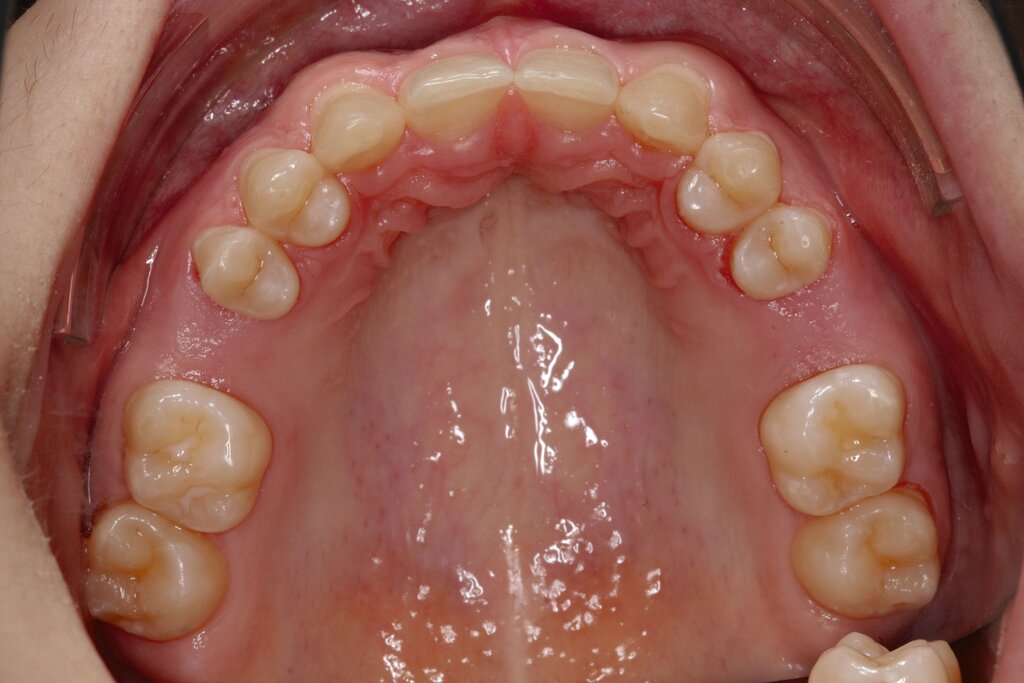

Bei dem gut zwölfjährigen Mädchen sind die seitlichen oberen Schneidezähne (Zähne 12 und 22) nicht angelegt. Zusätzlich zeigten sich verlagerte zweite obere Prämolaren.

b) im Oberkiefer von okklusal nach Mesialisierung von 13, 14 und 15 sowie 23, 24 und 25 und Lückenöffnung außerhalb der ästhetischen Zone mesial 16 und 26